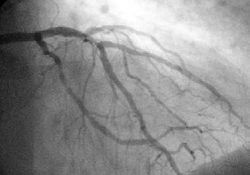

Angiography

Angiogram of the coronary arteries.

In difficult cases or in situations where intervention to restore blood flow is appropriate, coronary angiography can be performed. A catheter is inserted into an artery (usually the femoral artery) and pushed to the vessels supplying the heart. A radio-opaque dye is administered through the catheter and a sequence of x-rays (fluoroscopy) is performed. Obstructed or narrowed arteries can be identified, and angioplasty applied as a therapeutic measure (see below). Angioplasty requires extensive skill, especially in emergency settings. It is performed by a physician trained in interventional cardiology.